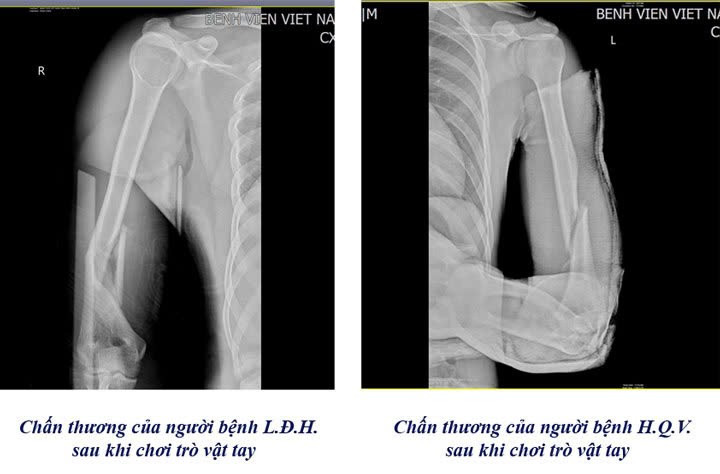

Gãy xương trên phim chụp của các bệnh nhân chơi trò vật tay - Ảnh BVCC

Có những trường hợp nhập viện trong tình trạng gãy nham nhở, gây khó khăn cho các bác sĩ trong việc đưa các mảnh xương về vị trí ban đầu, gia tăng nguy cơ tổn thương dây thần kinh quay, dây thần kinh trụ và mạch máu lân cận. Đa phần các trường hợp nhập viện đều ở độ tuổi học sinh, sinh viên.

Các trường hợp này thường phải tiến hành phẫu thuật kết hợp xương bằng nẹp vít. Đây là kỹ thuật hiện đại và phổ biến trong điều trị gãy xương cánh tay, mang lại hiệu quả cao giúp người bệnh gãy xương mau lành, cố định vững chắc vị trí gãy và tạo điều kiện thuận lợi cho quá trình liền xương.